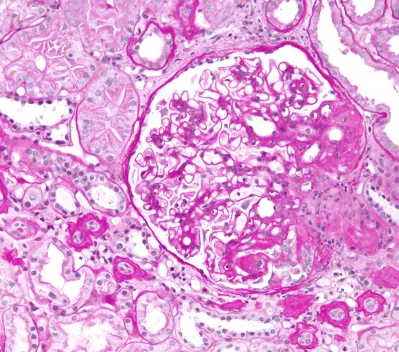

Световая микроскопия на современном этапе предполагает исследование почечной ткани после окрашивания различными методиками:

• окраска гематоксилином-эозином (для общего анализа структур);

• окраска по Массону (визуализация соединительной ткани);

• трихромальная окраска (для выявления фуксинофильных отложений);

• РАS-ШИК (для анализа мембран и дистрофии эпителиальных клеток);

• серебрение по Джонсу (исследование мембран);

• окраска по Вейгерту (исследование состояния сосудов);

• окраска конго-рот (идентификация амилоидных масс).

Отсутствие тех или иных методик окрашивания при выполнении световой микроскопии затрудняет постановку точного морфологического диагноза. Например, без выполнения серебрения по Джонсу нельзя сделать вывод о состоянии базальных мембран, что является важным компонентом верификации диагноза8.

Состояния, которые можно определить при помощи световой микроскопии:

• норма;

• сегментарный склероз/некроз;

• утолщение/нарушение структуры ГБМ;

• расширение мезангия/мезангиальная пролиферация;

• эндокапиллярная пролиферация;

• экстракапиллярная пролиферация.

Обзорное исследование биоптата включает оценку распространения и тяжести повреждений. Повреждение считается сегментарным для одного клубочка, если оно занимает менее 50% площади сосудистого клубочка, и глобальным, если занимает от 50 до 100% площади клубочка.

Тяжесть повреждения оценивается полуколичественно по балльной системе. Оценка варьируется от 0 до 3 или от 0 до 4 баллов, где 0 баллов означает отсутствие изменений, а 3 или 4 балла — выраженные изменения.

Основные гломерулярные повреждения, выявляемые при помощи световой микроскопии, включают увеличение или уменьшение размеров клубочка, изменения в количестве клеток клубочка, лобулярность (дольчатость), наличие некрозов, склероз, изменения клеток и базальной мембраны, изменение состояния просветов капилляров и Боуменовой капсулы, канальцев и интерстиция, а также сосудов.